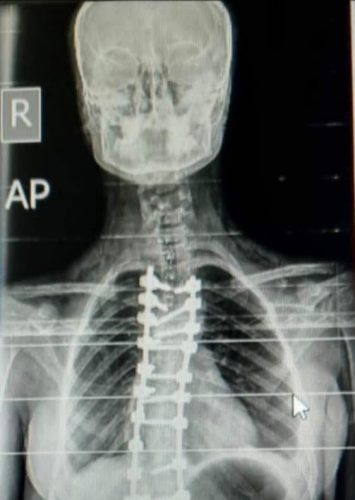

وأكد الدكتور فراس العبيدي، أحد رواد جراحة العمود الفقري في العراق، بمساهمته بشكل فاعل ليس فقط في إعداد وتدريب الكوادر، بل أيضًا في إجراء العشرات من عمليات تصحيح اعوجاج العمود الفقري في مدينة الطب بأيادٍ عراقية خالصة، والتي أصبحت اليوم تُجرى كإجراءات روتينية بفضل تراكم الخبرة والدعم المؤسسي.